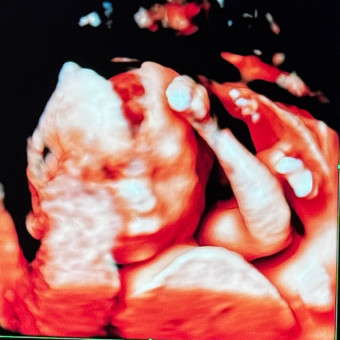

We can’t wait to welcome our baby girl into the world. Your love and support already mean so much — this list is just a way to help us get ready for her arrival. We’re so grateful to share this journey with you 💕Most wanted